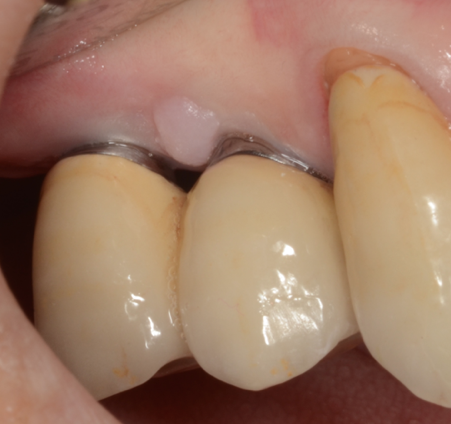

There are a wide variety of such interdental products on the market. For implant patients, the author recommends choosing an oral irrigator that pulsates and has at least two tips: the universal tip and the dental implant tip with three tufts. A Tufts University School of Dental Medicine study found a water flosser with implant tip was 145% more effective than string floss around implants when used in conjunction with a manual toothbrush.9 Significant reduction of gingival bleeding at 2 weeks and 30 days, respectively, were reported.9 Improvement in the health of tissues around implants can be seen in one patient who presented with inflammation around an implant (Figure 1), and another patient with a full-arch prosthesis that now has minimal-to-no plaque around both the top and bottom peri-implant tissues (Figure 2).

Improvement in tissue health around an implant after use of an oral irrigator.

Figure 1